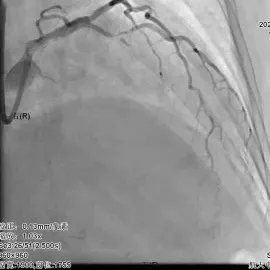

入院后第4天苏工介入团队为患者行冠脉造影术,提示前降支在发出第一对角支后呈现100%闭塞状态,第一对角支近段存在长节段病变,最大狭窄程度达90%。苏工副主任领衔的冠脉介入团队经多维度研讨,尝试开通前降支闭塞病变,开通后对介入术式进行评估。 经过多次反复尝试,导丝通过前降支闭塞病变,考虑第一对角支近段病变重,为分叉病变,术式采用DK-CRUSH,整个手术过程历时2小时,术后TIMI血流3级。

PCI术前